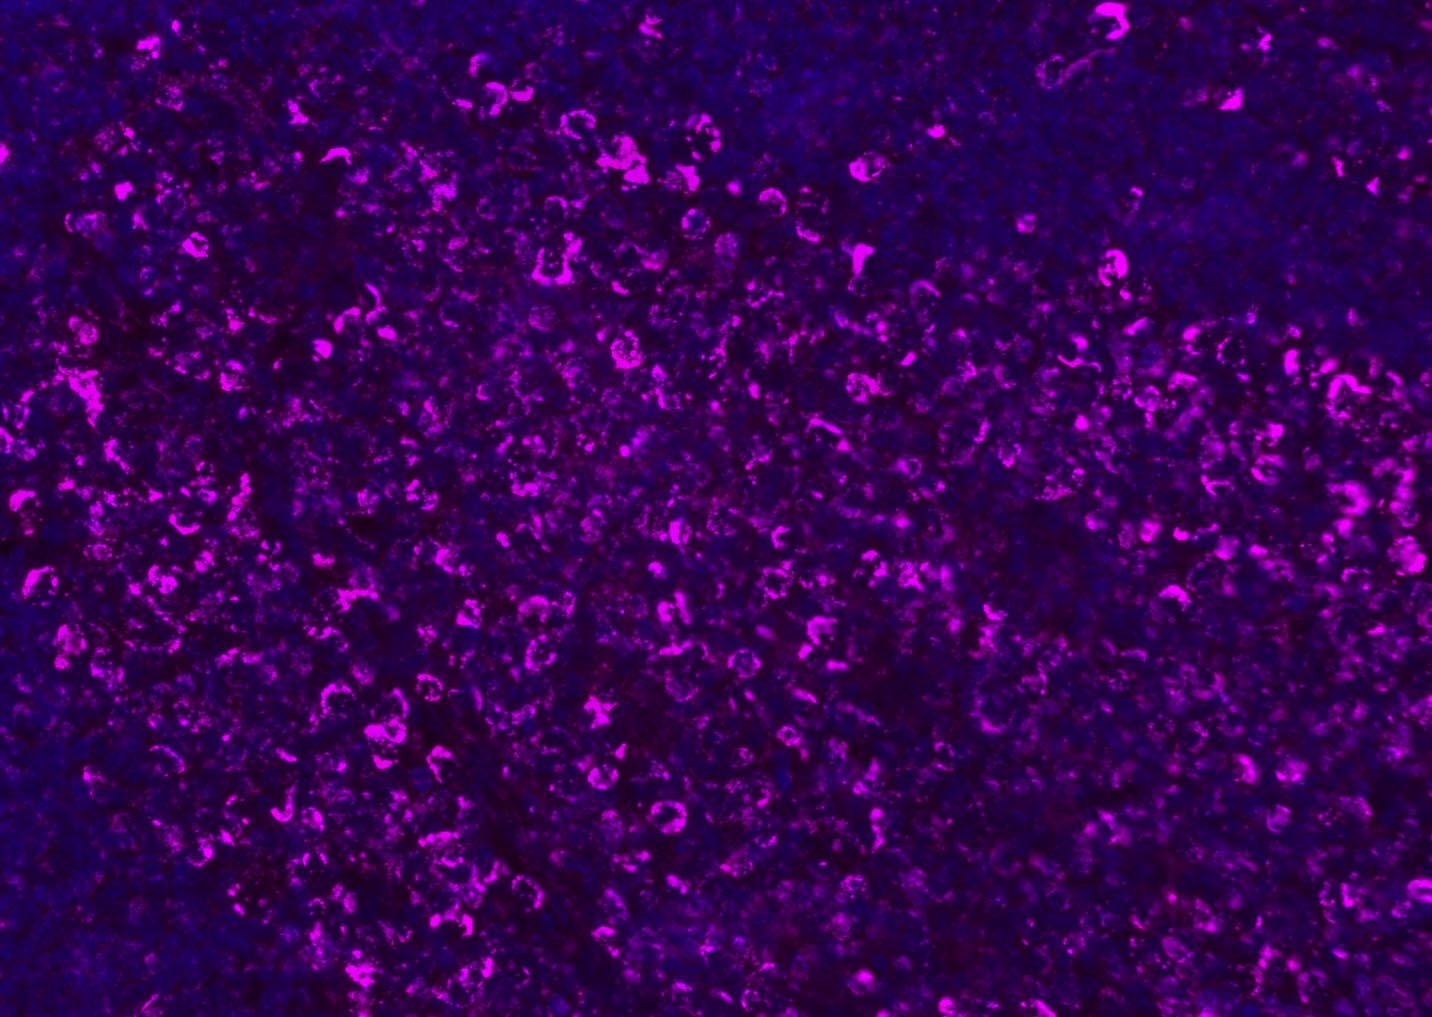

Tissue/cell: human lung carcinoma;4% Paraformaldehyde-fixed and paraffin-embedded;

Antigen retrieval: citrate buffer ( 0.01M, pH 6.0 ), Boiling bathing for 15min; Blocking buffer (normal goat serum,C-0005) at 37℃ for 20 min;

Incubation: Anti-CD8 Polyclonal Antibody, Unconjugated(bs-4914R) 1:200, overnight at 4°C; The secondary antibody was Goat Anti-Rabbit IgG, Cy3 conjugated(bs-0295G-Cy3)used at 1:200 dilution for 40 minutes at 37°C. DAPI(5ug/ml,blue,C-0033) was used to stain the cell nuclei